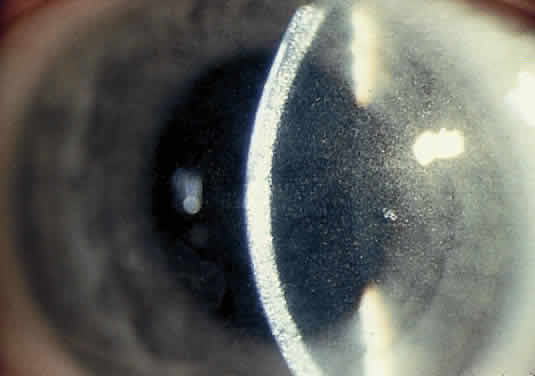

OCULAR FINDINGS. The outstanding clinical feature common to all three phenotypes is the corneal and conjunctival cystine crystal deposition (Figs. 3 and 4). Photophobia is often the only presenting visual symptom; this may be incapacitating and associated with blepharospasm.

Fig. 3. Cystinosis. Refractile crystals noted throughout the corneal stroma.

Corneal deposits appear as a layer of homogeneously distributed, fusiform or needle-shaped, iridescent crystals situated in the stroma beneath the epithelium. In the infantile form, anterior crystal deposition begins early in life (between 6 and 15 months of age) and proceeds posteriorly as the patient ages; deposition advances more rapidly in the periphery. The anterior location of the crystals may be associated with recurrent erosions.33 The depth of the stromal deposition and the density of crystals is always greater peripherally than centrally. More and larger crystals occur in the superficial stroma. No visual impairment occurs at this early stage. By the age of 7 years, most patients have crystals, either within or on the endothelial surface34,35; markedly decreased corneal sensitivity is also present.36 The spherical contrast sensitivity function is significantly lower in infantile cystinosis than in age-matched controls.37

The conjunctiva has a ground-glass appearance. Polychromatic, polymorphic, rectangular, or rhomboidal crystals can be seen with the biomicroscope.